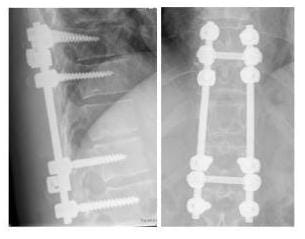

STABILISIERUNGSOPERATION AN DER WIRBELSÄULE

Röntgenbild ein Wirbelkörper wurde mit einem Doppelstabsystem überbrückt

Ein Wirbelkörper war auf Grund einer Tumorerkrankung nicht mehr belastbar und wurde mit einem Doppelstabsystem überbrückt. (Bilder: Orthopädie)